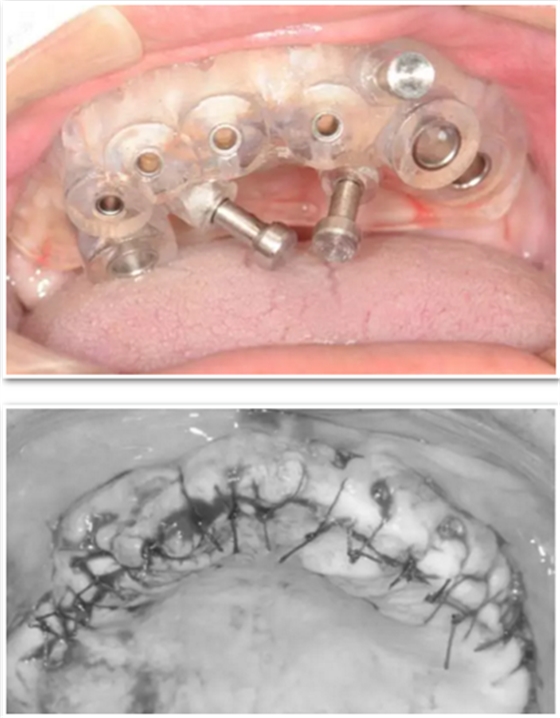

臨床手術(shù)

手術(shù)時,帶上導(dǎo)板,逐級備孔,在15和25的位置需要進(jìn)行內(nèi)提升,因此對于備孔深度的把控尤為重要,導(dǎo)板的作用得到了重大發(fā)揮。

去掉導(dǎo)板,進(jìn)行上頜竇內(nèi)提升,填入骨粉,植入種植體。

最后縫合。